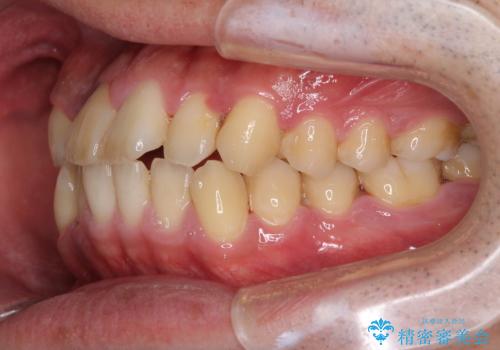

前歯のクロスバイトを改善 インビザラインによる矯正治療

- 前歯のクロスバイトを気にして来院された患者様です。

デコボコやクロスバイトが散見されたため、IPR(歯と歯の間を削る)によってスペースを獲得できるように設計し、インビザラインにより治療を行うこととしました。

上顎側切歯(上の真ん中から2番目の歯)が舌側転位している場合、インビザラインでは仕上げきれない可能性があり、更には無理して動かそうとすると歯髄壊死を起こすリスクが高いと言われています。

安全に治療を行う対策として、インビザラインで歯列を移動する前に、上顎前歯をワイヤー矯正で整え、その後上下歯列をインビザラインにて矯正治療を行うプランを提案しています。

今回は、ワイヤー装置を併用することなく治療を行い、トラブルなく、満足のいく歯列に整えることができました。